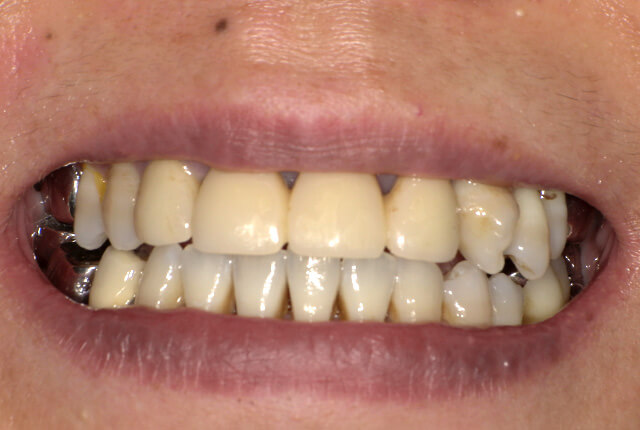

よく噛めず笑うと銀歯が目立つので気にされていました。

90分の治療で銀歯の状態からキレイな状態になります。噛み合わせの調整や審美面も使用しながら合わせます。

| 主訴 | ブリッジ脱離、しっかり噛めない |

| 診査診断 | 上顎歯牙欠損、歯周病、不良補綴、根尖性周囲炎。 不正咬合により噛み合わせのバランスが悪い事が原因により咬合治療が必要。 |

| 主訴 | 噛めない、食事がしっかりできる様になりたい。 |

| 診査診断 | 歯周病、歯の崩壊、不良補綴。 全顎的咬合異常、前歯の噛み合わせ、奥歯の噛み合わせに問題あり。 |